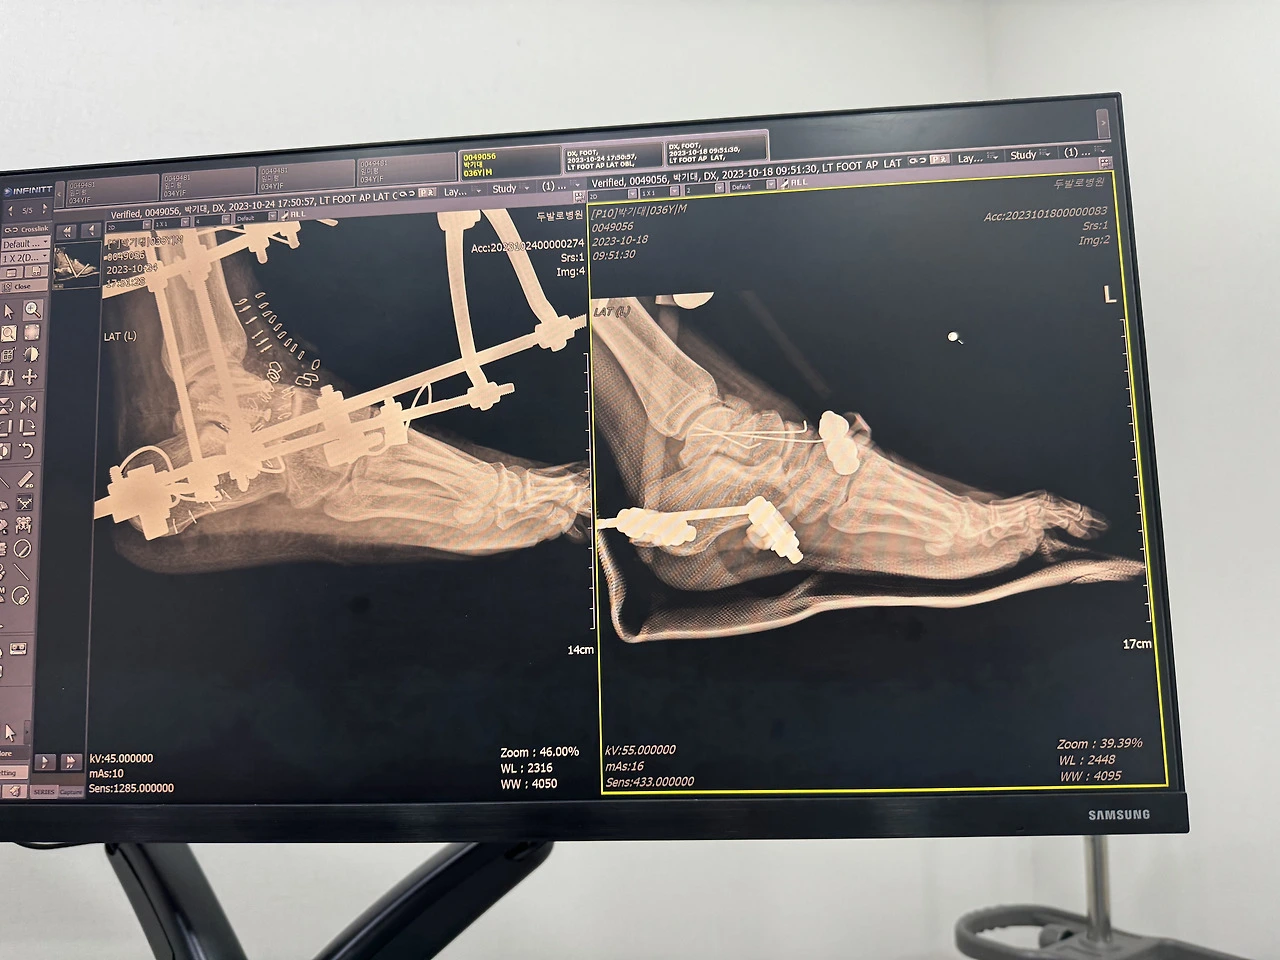

본 수술을 한 후 줄 곧 물리치료와 산소치료를 병행했다. 무거운 철제 외고정기를 차고 병동과 치료 실을 오가는 것은 쉽지 않았다. 수술부위가 조그만 닿아도 아플 것 같아 최대한 조심히 다녔다. 그리고 수술 부위가 잘 아물고 있다는 것을 의사 선생님이 확인했을 때 퇴원 날짜를 정 할 수 있었다. 그리고 퇴원 준비를 할 수 있었다.

퇴원을 하고 나서도 돌아다닐 수 있도록 목발을 짚는 법을 배웠다. 그리고 수술한 다리가 고정되어 있어 굳는 것을 방지하기 위해 간단한 발가락, 종하리 운동도 배웠다. 4주간 외고정기를 차고 있어야 하기 때문에 목발은 필수였다. 의사 선생님은 외고정기가 단단히 고정되어 있어서 밖으로 외출도 가능하다고 하셨다. 하지만 외고정기를 차고 밖으로 나갈 엄두가 나질 않았다.

오늘의 또 하나의 이슈는 항생제를 많이 써서 적혈구 수가 많이 줄어들었다는 것이다. 큰일인 줄 알았는데 항생제만 수액 항생제를 끈고 먹는 항생제로 바꾸고 지켜보기로 했다. 퇴원 약봉투에 항생제 약이 추가되었다. 나와 가족은 들은 수술한 거골이 붙지 않아 무혈성괴사가 일어나는 것을 무척 두려워했다. 거골이라는 부위는 피가 잘 안 통해 최악의 경우 뼈가 붙지 않아 괴사 될 수 도 있다는 것이다. 그냥 기다릴 수는 없다는 생각에 의사 선생님께 뼈에 좋은 다른 것이 없냐고 물어보았다. 의사 선생님은 고민을 하다가 메일 배부분의 지방층에 주사를 노을 수 있는 작은 기구를 처방해 주셨다. 정확한 건 아니지만 나중에 알고 보니 나이 든 사람들이 골다공증에 쓰는 치료제 같았다.

의사 선생님은 철제구조물의 지지대가 정강이 뼈에 박혀있는 부분과 수술로 절개된 부분의 소독을 집에서 해도 된다고 하셨다. 하지만 많이 걱정되었던 아빠는 일주일에 한 번씩 병원으로 나를 데려와 물리치료과 상처부위 소독을 하게 해 주셨다.